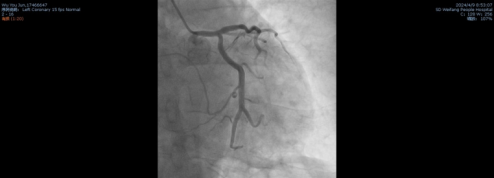

患者的一系列结果与症状都指向急性心肌梗死,立即在北辰院区行冠状动脉造影术,冠脉造影结果: